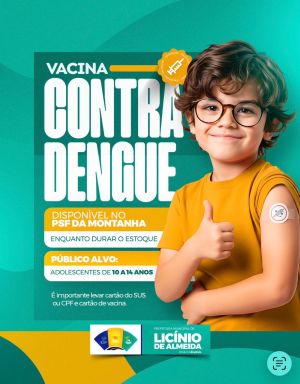

Licínio de Almeida inicia vacinação de adolescentes e intensifica combate ao Aedes Aegypti